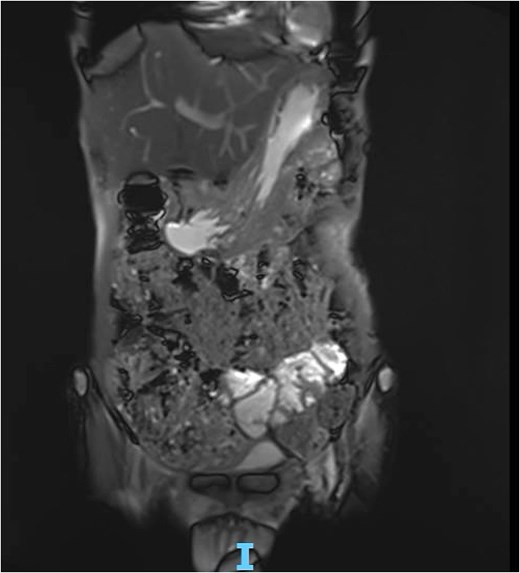

Magnetic resonance enterography (MRE) (Fig. 5): Gastric wall defect (~0.6 cm) communicating with the collection, consistent with a contained perforation. No evidence of inflammatory bowel disease.

MRE showing gastric wall defect (~0.6 cm) communicating with the collection, consistent with a contained perforation. No evidence of inflammatory bowel disease.